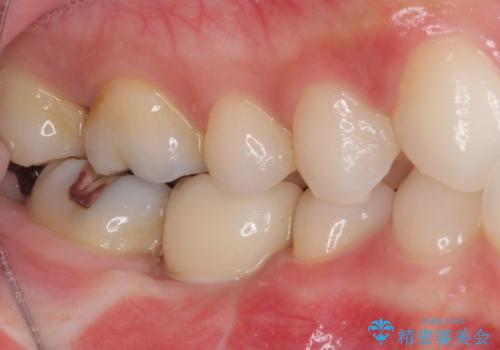

抜歯後にはストローマンSLActiveを埋入し、補綴治療を行うこととしました。

機能性と清掃性、更には審美性も考慮し、土台となるアバットメントにはジルコニアカスタムアバットメントを採用しました。

ジルコニアカスタムアバットメントは、歯肉ラインに金属が見えにくいというだけでなく、クラウンを装着する土台の形が天然歯と近い形態となるため、清掃性が高く歯肉が腫れにくいというメリットがあります。